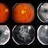

- 50-year-old white male. 20/15 OU. Proliferative diabetic retinopathy.